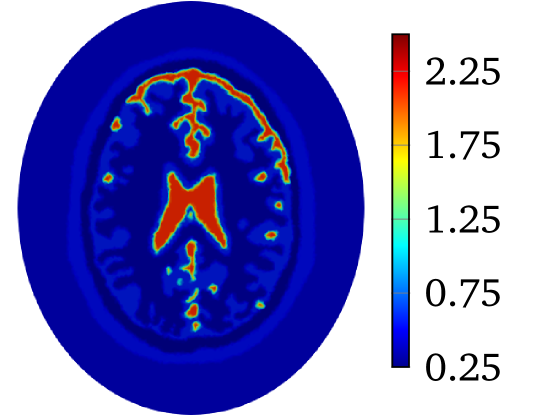

The second example is the human brain model shown in Figure 1(b). The considered tissues in this model include scalp (green, ), skull (blue, ), cerebro-spinal fluid (red, ), gray matter (yellow, ) and white matter (cyan, ). Refer to [5] for conductivities of different tissues. The shape of this model is close to an ellipse whose semi-major and semi-minor axes are and . The model is placed in an ellipse region with a background material (white, ). The semi-minor and semi-major axes of the region are and , respectively. The conductivity maps for the phantoms are piece-wise constant functions which will be mollified with

to produce with for 2D problem. The constant is selected so that . The value of is and for heart-lung model and human-brain model, respectively. The true smoothed distributions of for the two models are shown in Figure 2.